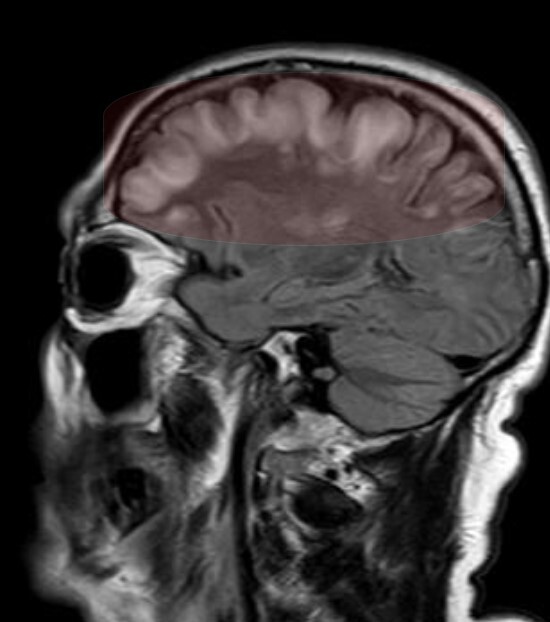

На 3й день после травмы из комы так и не вышла, посему сделали МРТ, на котором обнаружились участки повышенного сигнала на Т2-взвешенных изображениях на границе серого и белого вещества фронтально и темпорально справа, а также в область правого таламуса и в заднем отделе мозолистого тела т.н. сплениуме:

которые визуализировались и на FLAIR:

Очаги показывали также ограниченную диффузию на DWI-изображениях:

Ну и в довесок на SWI-изображениях (специальная импульсная последовательность, взвешенная по магнитной восприимчивости, усиливает сигнал от продуктов распада гемоглобина, что значительно повышает способность распознавать мельчайшие кровоизлияния в головном мозге) были выявлены очаги микрокровоизлияний в поражённых участках + в верхней ножке мозжечка и вдоль кортико-спинального тракта справа (чёрные пятна на изображениях):

Тут позволю возразить: представленное выше - одно из встречающихся тяжёлых последствий черепно-мозговой травма, а именно т.н. ДАП или диффузное аксональное повреждение:

Диффузное аксональное повреждение (ДАП) - это тяжелая форма травматического повреждения головного мозга возникающая за счет воздействия сдвигающих сил. Диффузное аксональное повреждение потенциально трудно диагностировать, поскольку проявления при компьютерной томографии могут быть едва различимы, однако оно может приводить к тяжелым неврологическим нарушениям.

В нашем случае это было ДАП 3 (максимальной) степени тяжести.